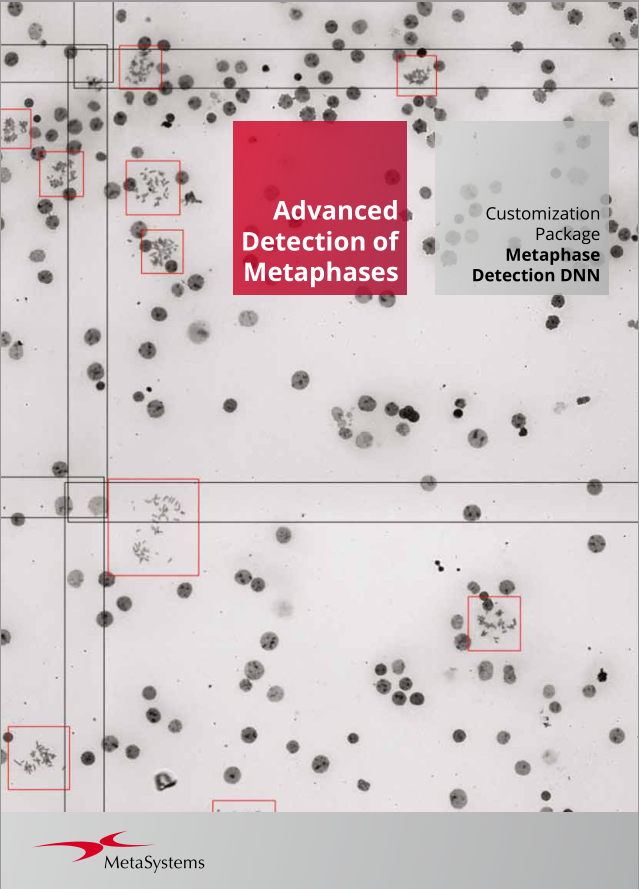

Given the variability of each microscopic sample, automated imaging demands flexibility. Metafer's distinctive concept provides an effective solution: user-trainable classifiers accurately establish imaging standards, and by selecting the relevant classifier, the integrated scanning system swiftly transitions to the next task.